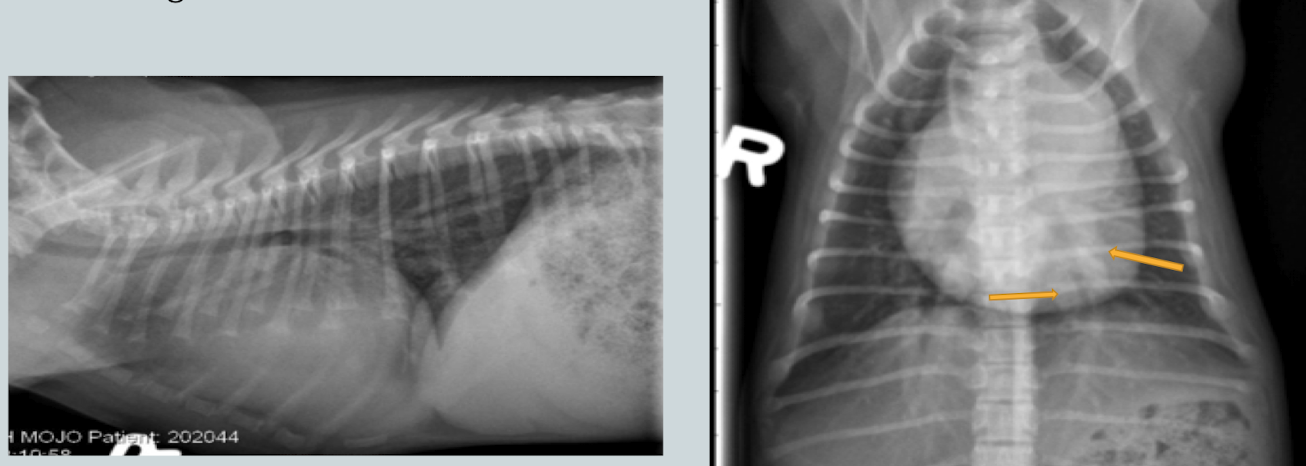

Lucy is a 9yo Fs DSH that the owner says seems to be trying to cough up hairballs lately. He owner books her a veterinary appointment today because she notices that she is breathing faster lately.

Lung pattern?

ddx?

Diffuse bronchial pulmonary pattern (donuts and tram tracks)

ddx: feline asthma